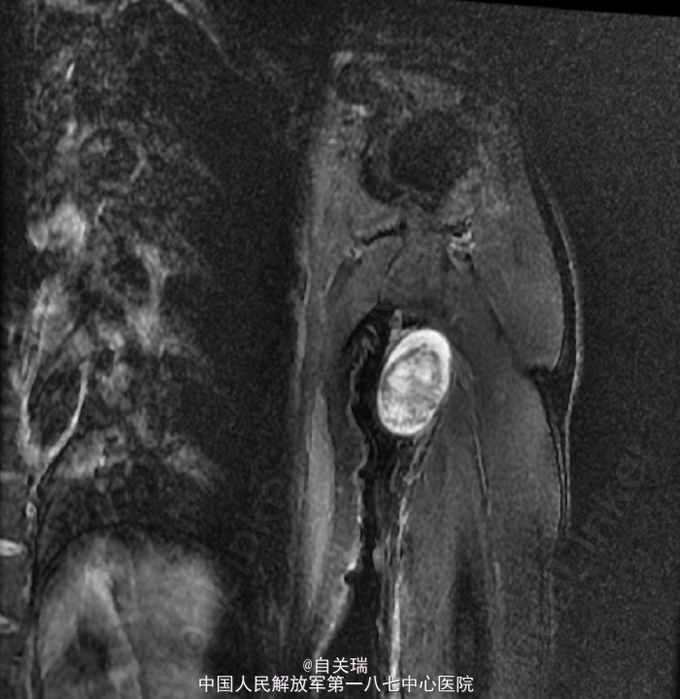

左上臂近端内侧可及约4CM*5CM的肿块,质韧,周围皮肤无红肿,触摸可出现左手内侧麻木,未见有肌肉萎缩,肢端血供感觉良好。MRI: 左上臂上段内侧皮下良性占位,神经鞘瘤可能.

初步诊断:左上臂神经鞘瘤. 全麻下行“左上臂神经鞘瘤切除术”.